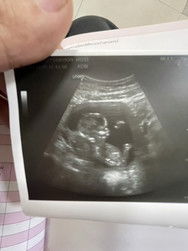

วันนี้ไปฝากครรภ์ตามรอบปกติ 23 wks ก่อนหน้านี้ไปซาวน์ MFM มา หมอที่เชี่ยวชาญลอกว่าหัวใจยังไม่ชัด อาจเพราะยังเล็กไป นัดอีกหนึ่งเดือนคือวันพรุ่งนี้ สาวนวันนี้หมอซาวหัวใจดูคร่าวๆให้ บอกว่าผนังหัวใจด้านซ้ายเจริญเติบโตไม่ค่อยเต็มที่ แต่ต้องให้หมอที่เชี่ยวชาญดู หมอบอกว่าหากมันผิดปกติจริงๆ อาจจะต้องยุติการตั้งครรภ์ ถ้าเกิดผ่าคลอด โอกาสรอดน่าจะน้อย ถ้าพูดกันตรงๆ แต่ทั้งนี้ทั้งนั้นต้องดูผลซาว MFM พรุ่งนี้ วันนี้น้ำหนักกว่าน้อย แค่ 450 g เอง รู้สึกเป็นกังวล เสียใจมาก บอกไม่ถูกเลยค่ะ ตั้งแต่ออกจากคลินิกมายังร้องไห้เป็นระยะๆอยู่เลย กลัวมากๆ ไม่อยากให้เขาเป็นอะไร อยากให้เขาปกติ อยากให้น้ำหนักลูกเรามากกว่านี้ โปรตีนก็พยายามกินเยอะมากๆแล้วนะคะ #ขอบคุณสำหรับคอมเม้นล่วงหน้าค่ะ #ท้องแรก #กังวลกลัวจะอันตราย